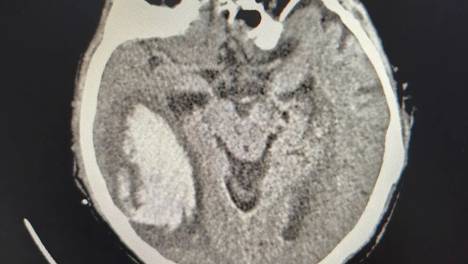

这场与“死神”的博弈,他们赢了!

吴爷爷的成功救治,并非偶然,而是北京老年医院神经外科团队深耕老年神经重症领域多年的必然成果:在经验积累上,团队年均独立完成老年脑出血、颅脑创伤等手术80余例,对合并心脑血管病、糖尿病等基础病的高龄患者,有着一…